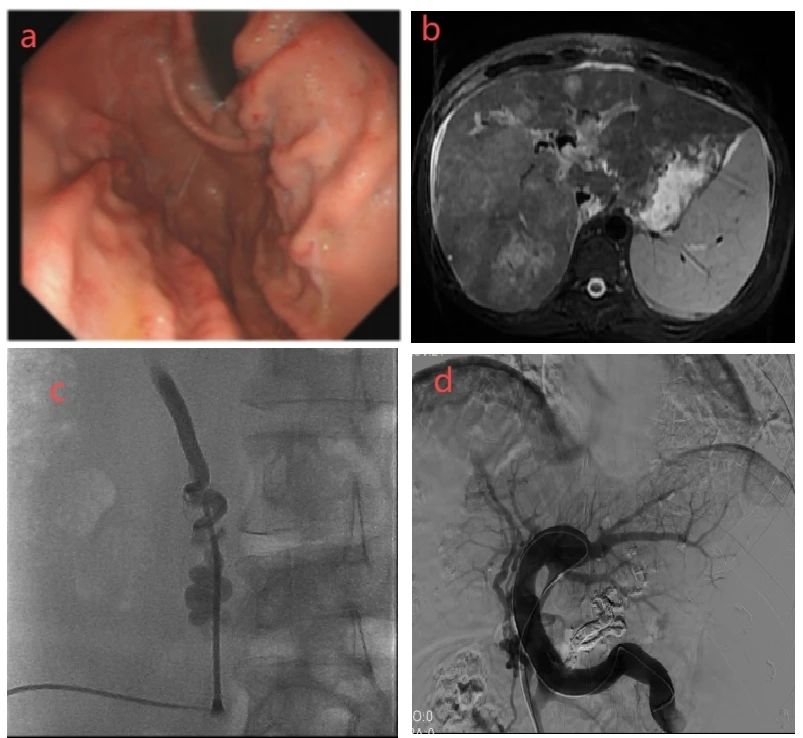

a.患者消化道出血前3个月胃镜提示食管胃底静脉曲张;

b.肝内多发病灶伴门静脉癌栓;

c.B超引导下经皮穿刺脐静脉成功;

d.经脐静脉入路导管进入胃底静脉栓塞成功